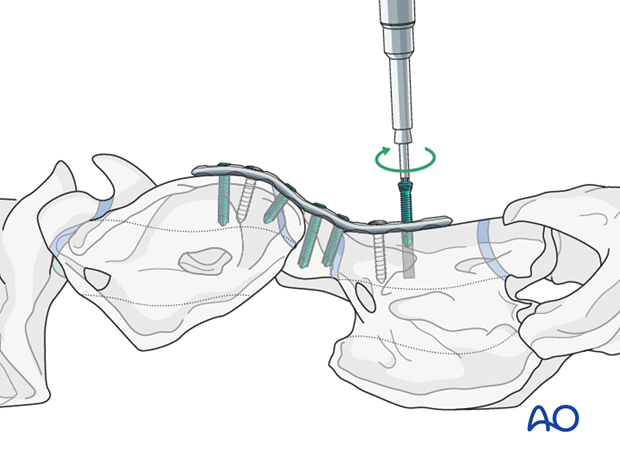

The use of a locking compression plate (LCP) is preferred for fracture fixation of the vertebrae. According to the size of the patient, a small or broad 3.5/4.0 or 4.5/5.0mm LCP is used.

Alternatively, a human distal femur plate can be used to improve the arthrodesis of C1-C2.

Minimal plate bending is needed.

With the reduction forceps in position, the appropriately sized plate is applied to the ventral aspect of C1 and C2.

One cortex screw is inserted into each vertebra in load fashion. The correct length of the screws is determined with the help of fluoroscopy.

Note: Attention must be paid not to damage the spinal cord.

The remaining holes are filled with locking-head screws.